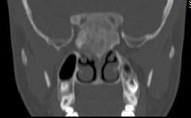

问题 女,17岁,鼻阻塞、头痛两年.如图所示符合筛骨病变最可能的诊断是()

选项 A.成骨肉瘤骨 B.纤维异常增殖症 C.软骨瘤 D.骨瘤 E.骨化性纤维瘤

答案 E